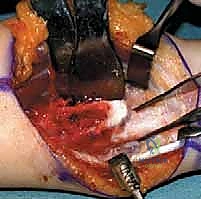

1. استئصال الأورام العظمية الغضروفية (Excision of Osteochondromas)

الخطوة الأولى هي إزالة الزوائد العظمية التي تسبب الاحتكاك وتعيق حركة المفصل. يتم ذلك بحذر شديد لتجنب الإضرار بصفيحة النمو المتبقية أو الأعصاب والأوعية الدموية المجاورة.

2. تحرير الشد الكعبري الزندي (Untethering)

يتم تحرير الأنسجة الرخوة والأربطة المتقلصة التي تربط بين عظمتي الكعبرة والزند، مما يسمح للعظام بالتحرك بحرية أكبر استعداداً للتصحيح.

4. القطع العظمي التصحيحي للكعبرة (Radial Corrective Osteotomy)

إذا كان انحناء الكعبرة شديداً، يتم إجراء قطع عظمي في الكعبرة لتعديل استقامتها. يتم تثبيت العظم في الوضع الجديد باستخدام شرائح ومسامير معدنية متطورة (Plates and Screws) لضمان التئام مثالي.